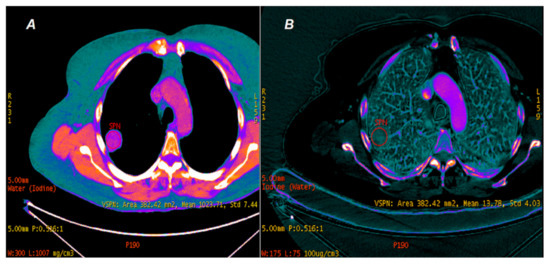

2. Materials and Methods

2.2. CT Scanning Parameters

2.3. Data Analyses

3. Results

3.1.1. Photon Interaction with Iodine Contrast Agent Accumulated in Lung Tumors

3.1.2. Comparison of Iodine Concentration in IC Maps, Water Concentration (WC) and Radiation Absorption in Lung Tumors in AP and VP of DECT Examination